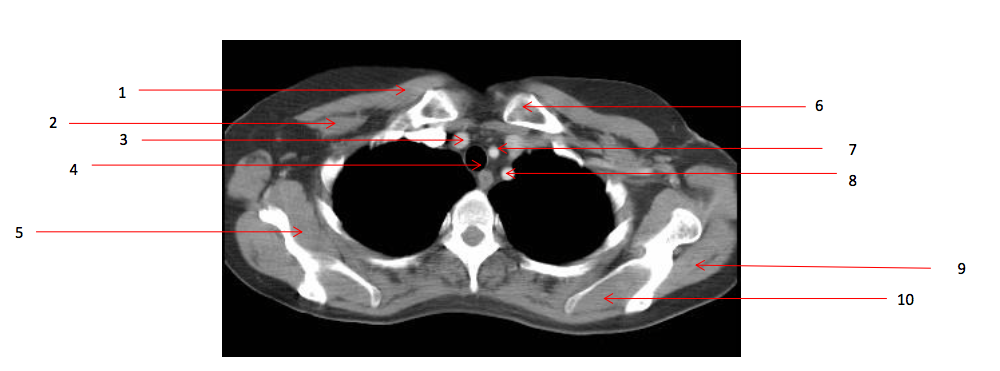

Number 2?

Rt pectoralis minor muscle

Number 6?

Lt clavicle

Number 10?

Lt supraspinatus muscle

Number 1?

Rt pectoralis major muscle

Number 8?

Lt subclavian artery

Number 4?

Trachea

Number 7?

Lt common carotid artery

Number 5?

Rt subscapularis muscle

Number 3?

Brachiocephalic artery